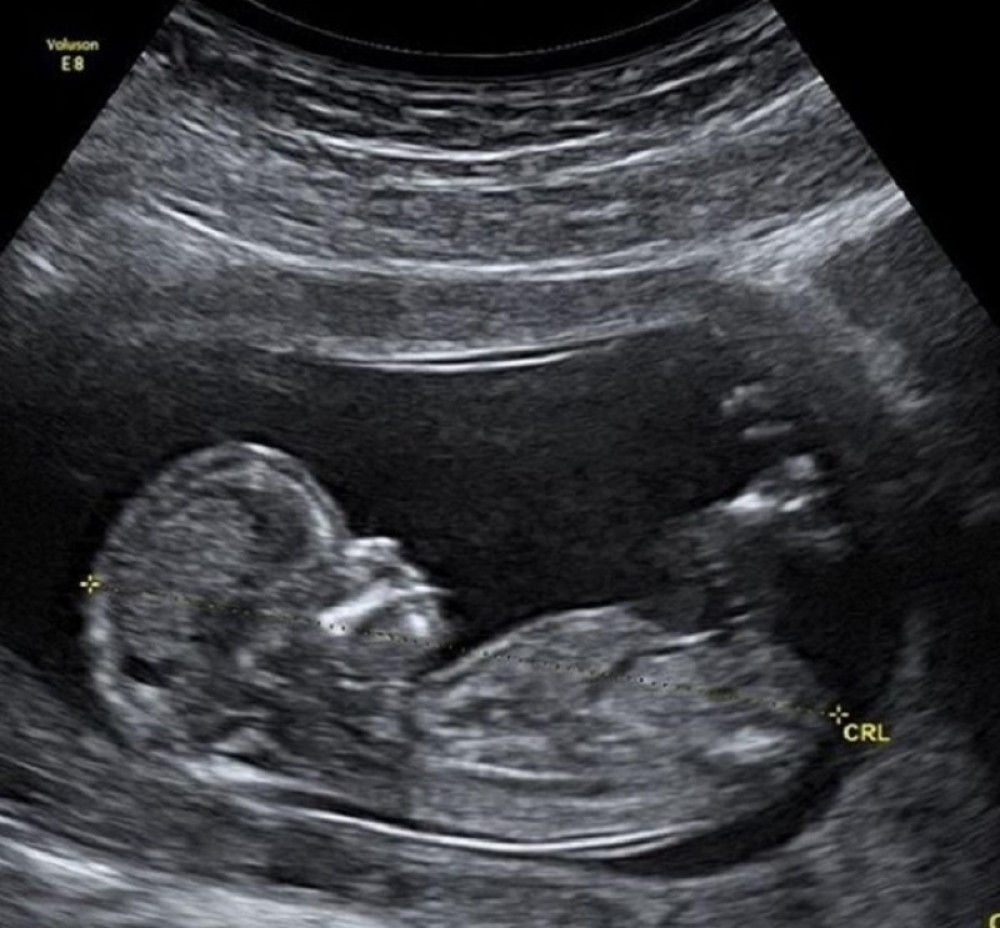

ULTRA ZVUK U 16. NEDELJI

Ovako izgleda beba koja štuca u materici (VIDEO)